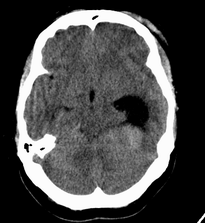

患者,女性,33岁,外伤检查发现,既往没有明显类似病史。

左侧脑室内软组织肿物,内部见多发不规则钙化,边界清楚锐利,有分叶。相应左侧脑室扩张。常见的不外乎3种病:室管膜瘤,脑膜瘤,脉络脉丛乳头状瘤。脑膜瘤分叶较少见,脉络脉丛乳头状瘤钙化较少见,因此,室管膜瘤可能性最大。

左侧脑室内见不规则略高密度团块影,边缘分叶,内见多发不规则钙化,病灶与侧脑室壁关系较为密切,左侧脑室扩大。考虑室管膜瘤可能性较大,其次为脑膜瘤,脉络丛乳头状瘤的可能性最小。

侧脑室三角区占位,首先考虑脑膜瘤,其次考虑室管膜瘤,室管膜瘤相对密度混杂一些,低一些。脉络丛乳头状瘤可能性不大,因为没有脑脊液明显增多改变,而且成人多在四脑室。

左侧侧脑室内分叶状肿块,其内见块状钙化,见左侧脑室阻塞性积水.考虑:脉络丛乳头状瘤

因病人无交通性脑积水,故脉络丛乳头状瘤不支持,脑室内脑膜瘤及室管膜瘤均有可能,病灶密度较高,前者可能性更大,建议结合增强检查。

左侧脑室后角不规则形,边界尚清的等密度肿块,肿瘤内有钙化。考虑脑膜瘤或室管膜瘤。